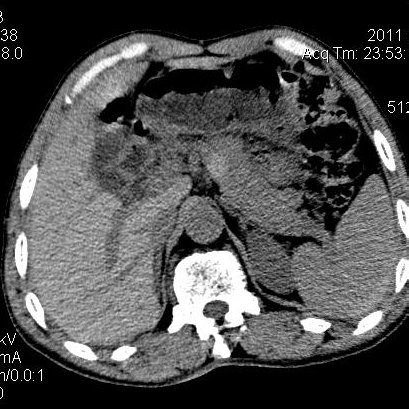

肝左叶发育异常

男性,55岁,骑摩托车摔倒后入院,自述右上腹疼痛

[backcolor=#FF0000]第一次诊断的时候也是这么肯定,可是床旁超声检查并没有发现明显异常,而且患者的一般症状都良好。还好临床只是保守治疗,没有立即手术,第二次复查的时候没有一点变化,又做了MRI检查,没有血肿,

这是一例肝左叶发育异常的,很个性吧~[/backcolor]